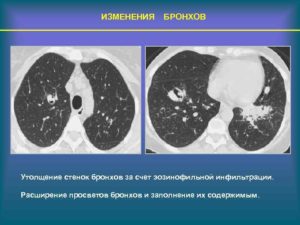

• Малоструктурность корня; • Контуры легочной артерии и вены расширены, нечеткие; • Рисунок усилен, изменен; • Утолщение бронхиальной стенки;

• «Трамвайные рельсы» — чередование полос за счет усиленного кровоснабжения периферии бронхов с полоской просветления за счет бронхиальной задержки воздуха.